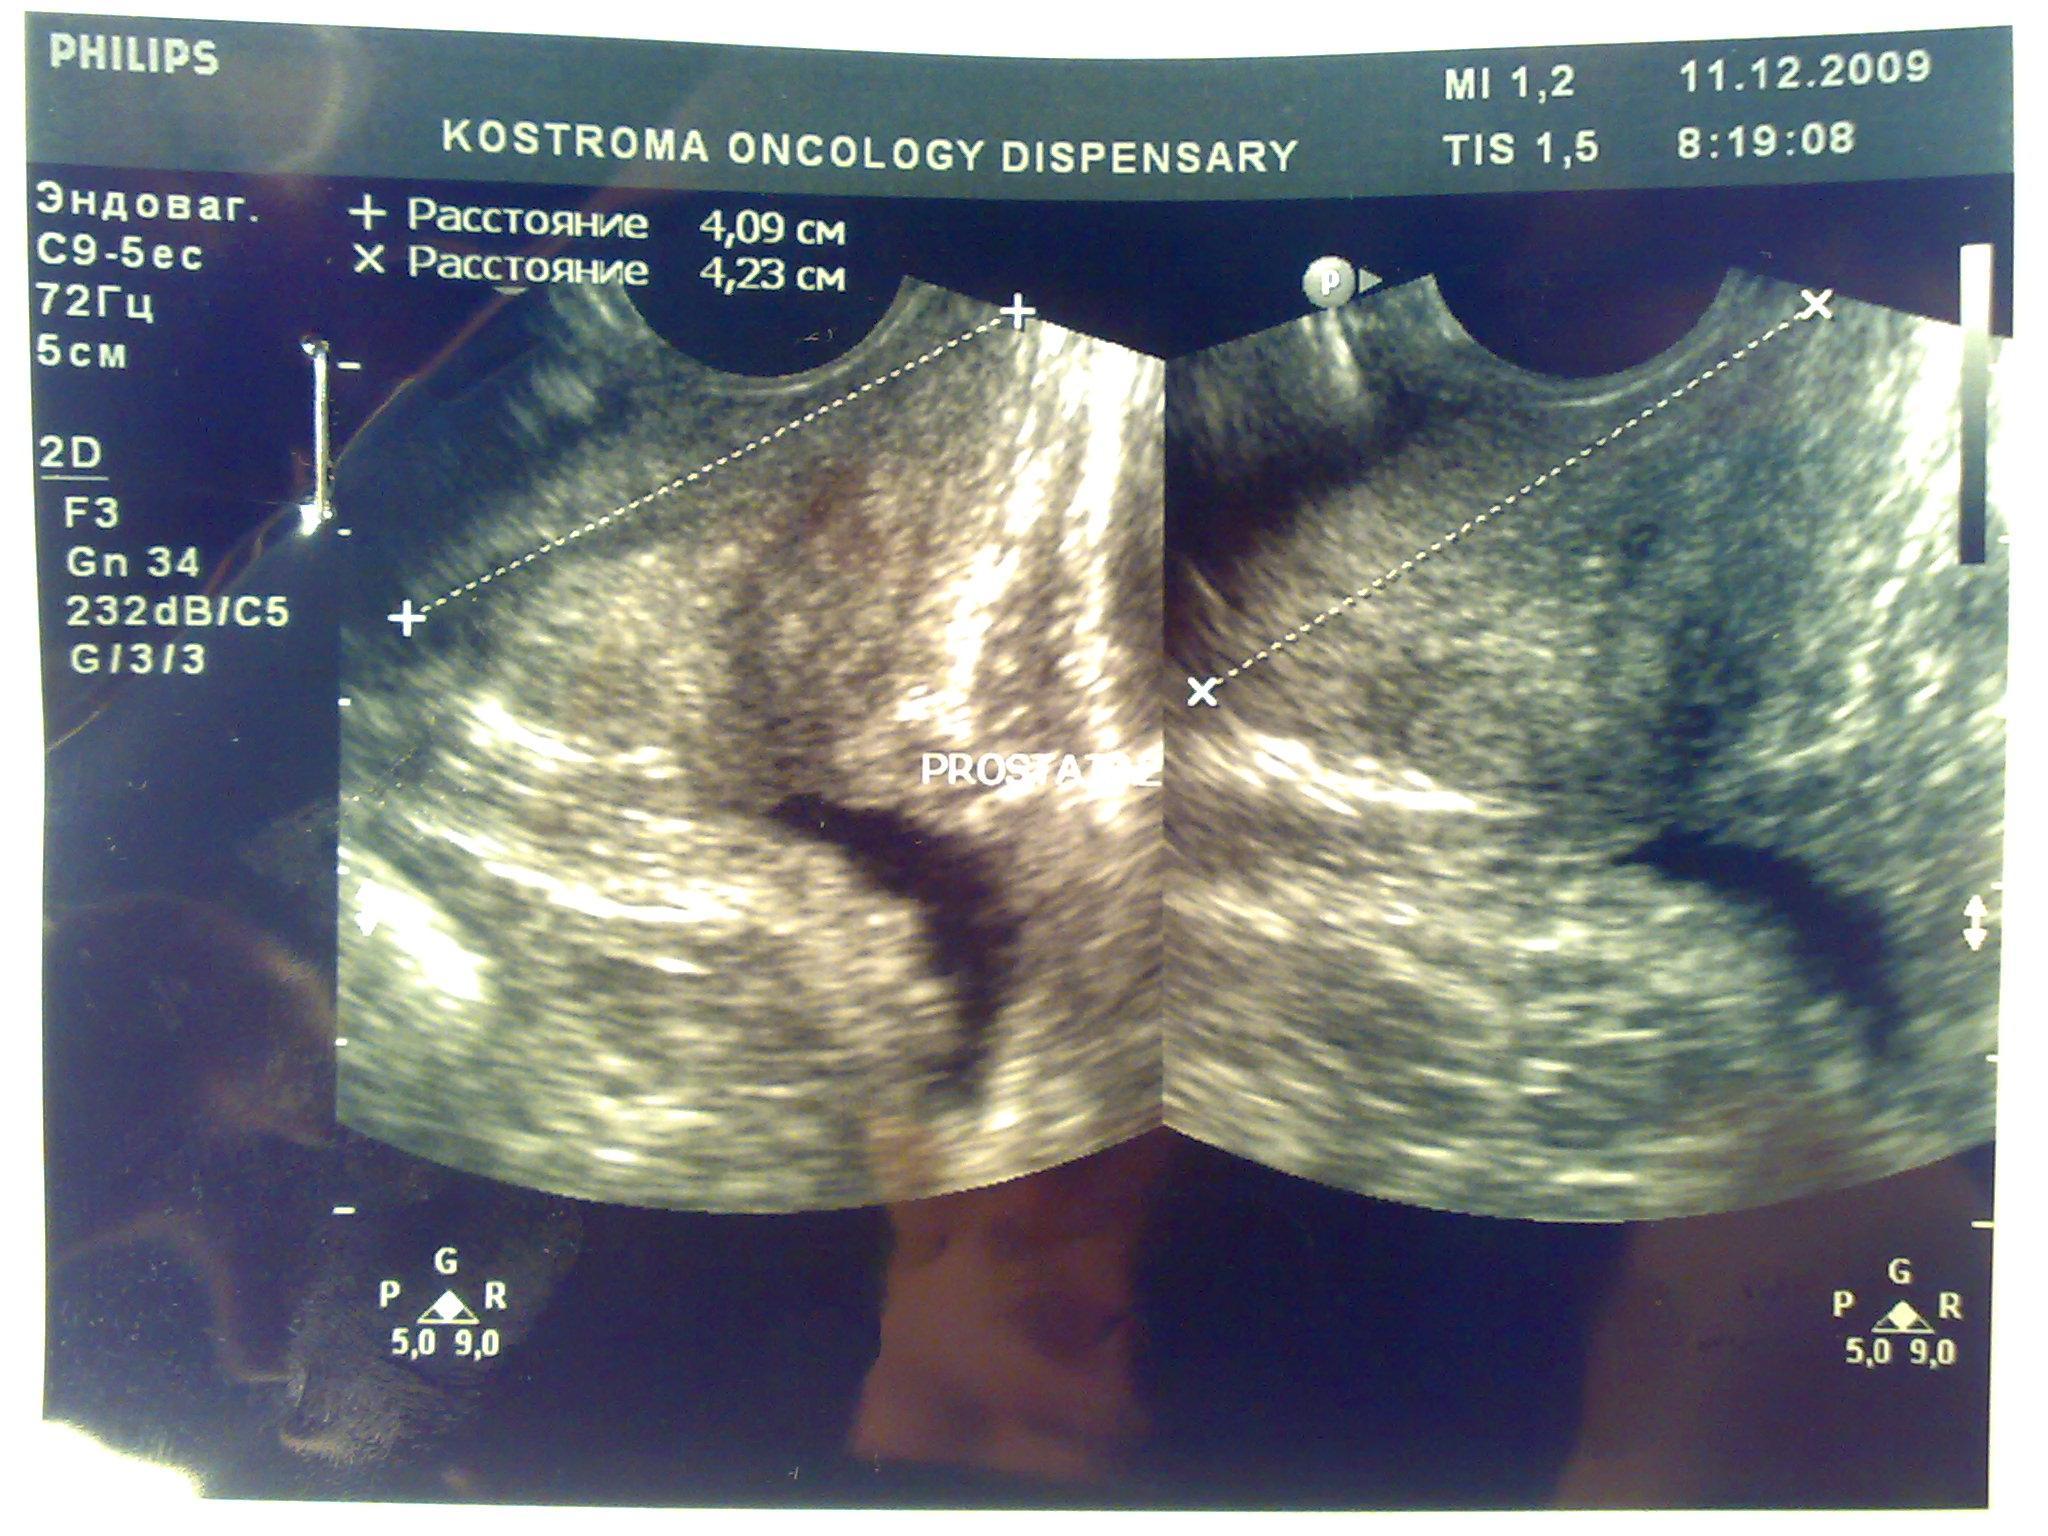

Доброго времени суток. В начале декабря сходил в банное заведение, употребил там пиво, вечером был сексуальный контакт с постоянной партнершей, на утро у обоих появилось жжение при мочеиспускании, у меня покраснение губок полового члена, умеренные выделения прозрачные, анализы крови и мочи в норме, ПЦР у обоих отрицательные. У девушки соэ 28, лейкоциты в моче выше 200, у меня все в норме, бак посев отделяемого из уретры выявил обильный рост Ешерихии коли, принимал внутремышечно Цефотаксим по 1г 2раза в день в течении 5 дней, во время лечения появилось жжение и дискомфорт в промежности. Трузи показало увеличение простаты, расширенные семенные пузырьки около 3 мм, кальцинатов и инфильтратов нет, в область мочевого пузыря не вдается, остаточное количество мочи около 10 мл, кол лейкоцитов в отделяемом из уретры 5-8 в поле зрения. Сейчас принимаю по назначению уролога Нолицин 400 мг по таблетке два раза в день, Палин 250 мг по 1 два раза и азитромицин 250 по одной раз в сутки, свечи на ночь Простатилен курс на 10 дней, уже прошло восемь массажей улучшение незначительное, симптомы в обшей картине сохраняются, железа со слов уролога стала более упругой и меньших размеров. У меня стала страдать эрекция, полной уже нет около 2 месяцев. После эякуляции хочется мочится, неприятные скребущиеся ощущения в промежности, сперма раньше выстреливала, а сейчас вытекает, выстреливает только первая порция, появились боли в мошонке слева, особенно после массажа, подскажите пожалуйста что делать, как лечится, какие еще анализы сдавать. Прикреплены снимки узи.Заранее благодарен.